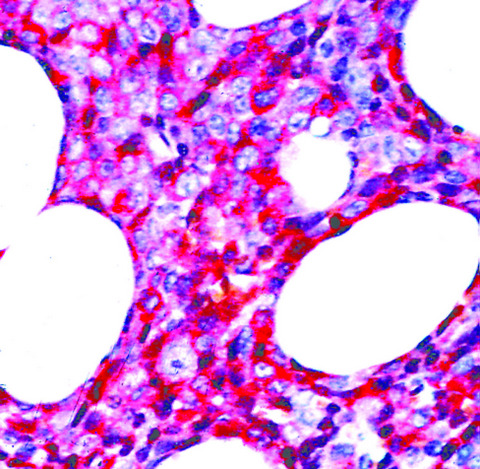

Microscopic (histologic) description

- Within the macules and plaque, mast cells are predominantly in papillary dermis

- Mast cells are round or spindle shaped with abundant eosinophilic cytoplasm, distinct cytoplasmic boundaries, large pale nuclei

- Eosinophils are often present

- Also edema of papillary dermis, subepidermal vesiculation

Microscopic (histologic) images